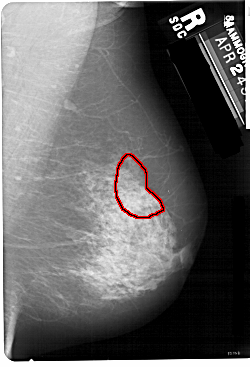

FILE: A_1127_1.RIGHT_CC.OVERLAY

TOTAL_ABNORMALITIES 1

ABNORMALITY 1

LESION_TYPE MASS SHAPE ARCHITECTURAL_DISTORTION MARGINS SPICULATED

ASSESSMENT 5

SUBTLETY 1

PATHOLOGY MALIGNANT

TOTAL_OUTLINES 2

BOUNDARY

CORE